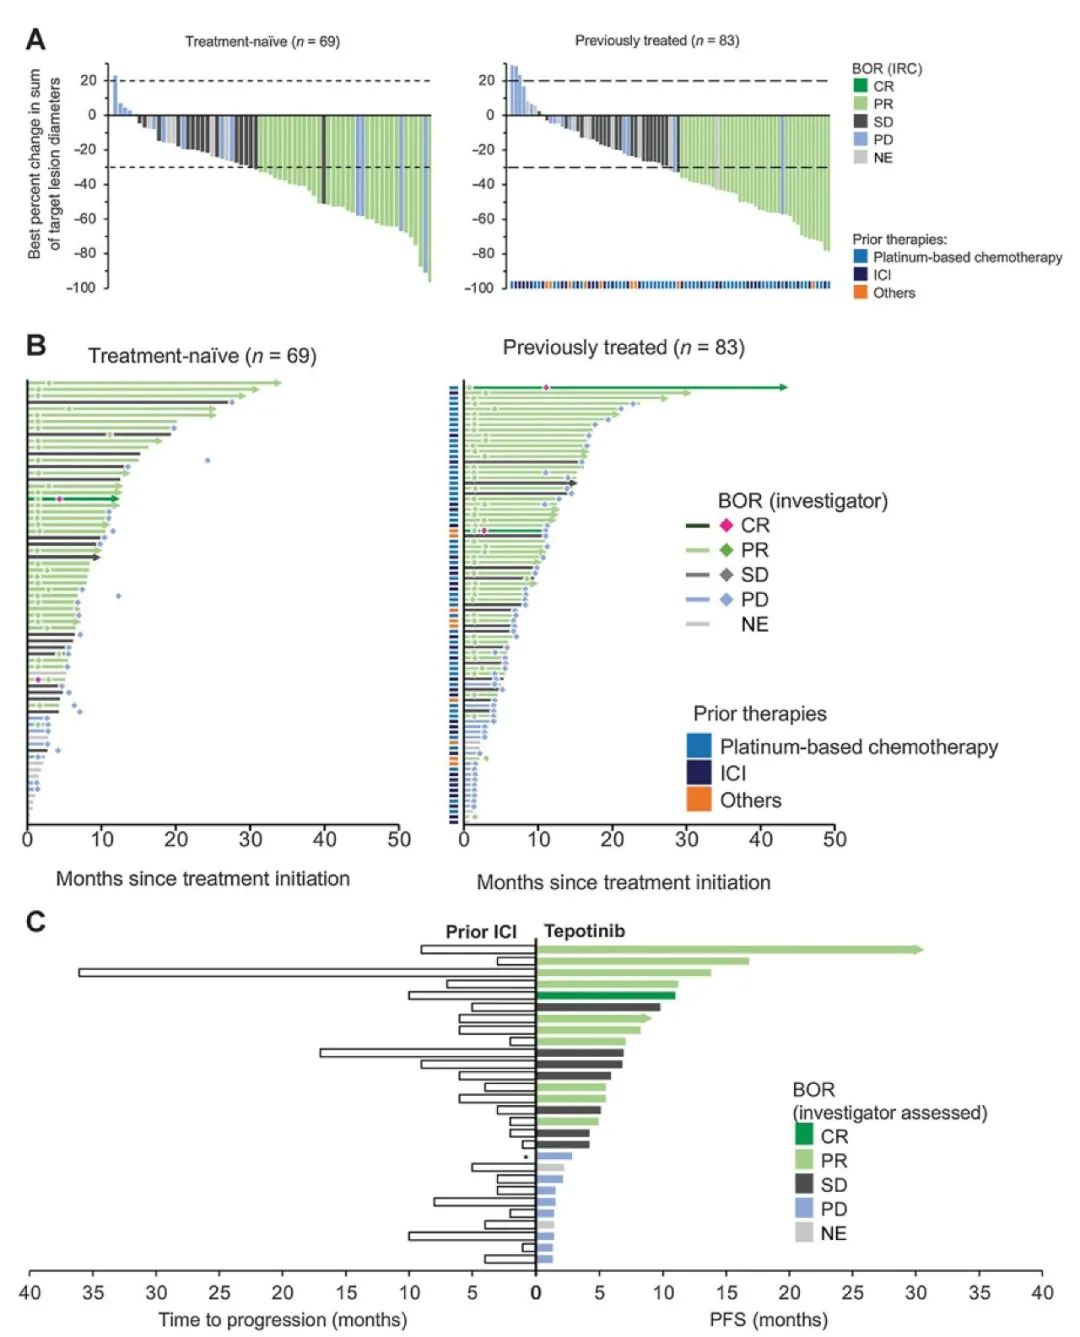

近年来,何志勇主任团队在双倍剂量伏美替尼治疗三代EGFR-TKI耐药的临床实践中,做了临床层面的探索,并总结了临床经验。近2年来,团队共应用双倍剂量伏美替尼18例,其中,3例是初治脑转移患者,15例是三代EGFR-TKI耐药且经历多线治疗后的患者,治疗都能达到不同程度的肿瘤缩小,总体缓解率为86%(13/15),中位疾病缓解时间为4个月,最长的超过17个月。

另据介绍,三代EGFR-TKI耐药后肺癌患者的治疗,是目前临床上的难点和热点。近年来,何志勇主任团队致力于在临床中探索不同的行之有效的策略。除了双倍剂量伏美替尼,团队还采用节拍治疗克服三代EGFR-TKI耐药,总结了28例患者的临床数据,疾病控制率达到89.3%

“节拍治疗适用于三代EGFR-TKI治疗后无症状缓慢进展的患者,双倍剂量伏美替尼适合于肿瘤还依赖EGFR信号通路的无症状缓慢进展或全身控制良好的脑转移复发患者。”何志勇主任解释道。另外,三代EGFR-TKI联合抗血管靶向药物、或联合局部放疗,也是团队长期在临床探索的有效的治疗策略。